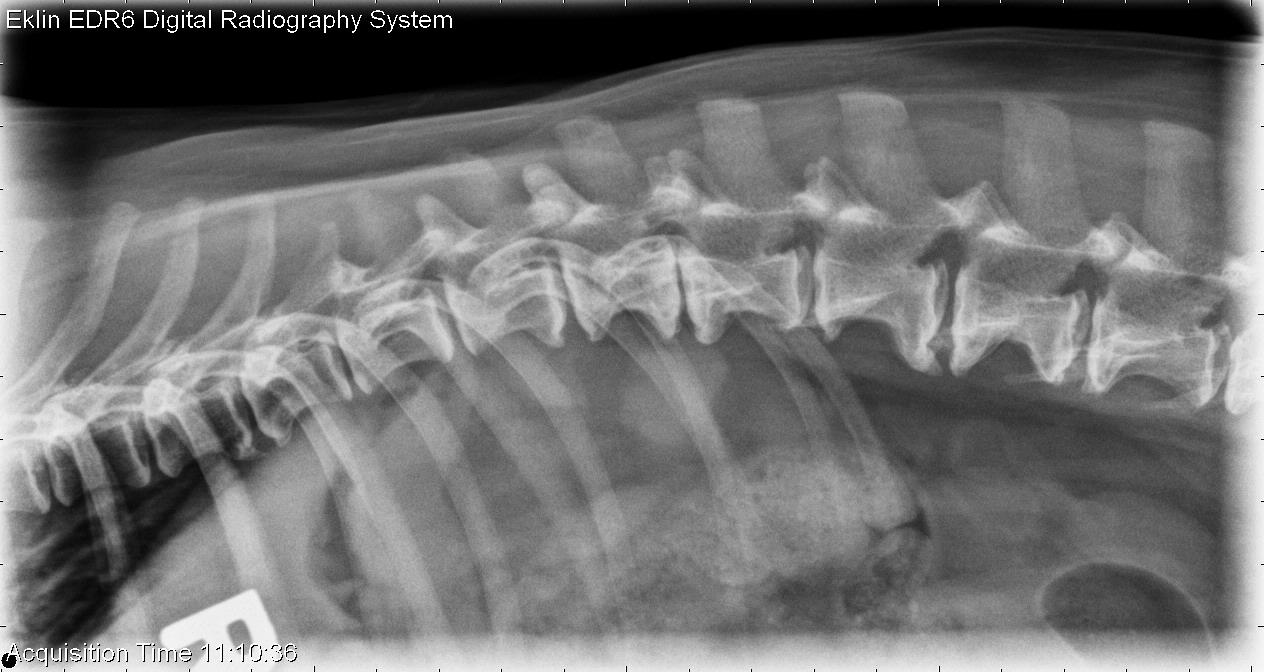

This week’s case is a 15-year-old female neutered Dachshund with several weeks history of non-ambulatory paraparesis. The tentative diagnosis is T3-L3 myelopathy. What are your findings?

On radiographs of the spine, there is scleroisis of the L6 vertebra most apparent on the lateral projection. On the ventrodorsal projection, there is loss of the cortical bone of the lamina at this level. The intervertebral foramen at L6-7 is irregular and enlarged. There is multifocal intervertebral disc space narrowing including T12-13, T13-L1, and L3-4, as well as spondylosis deformans throughout the spine.

The lysis and sclerosis of the L6 vertebra are consistent with an aggressive lesion, most likely neoplasia.

An MRI was performed, demonstrating a compressive mass in the L5-L7 region with spinal cord compression. Fine needle aspirate revealed malignant neoplasia, most likely sarcoma.